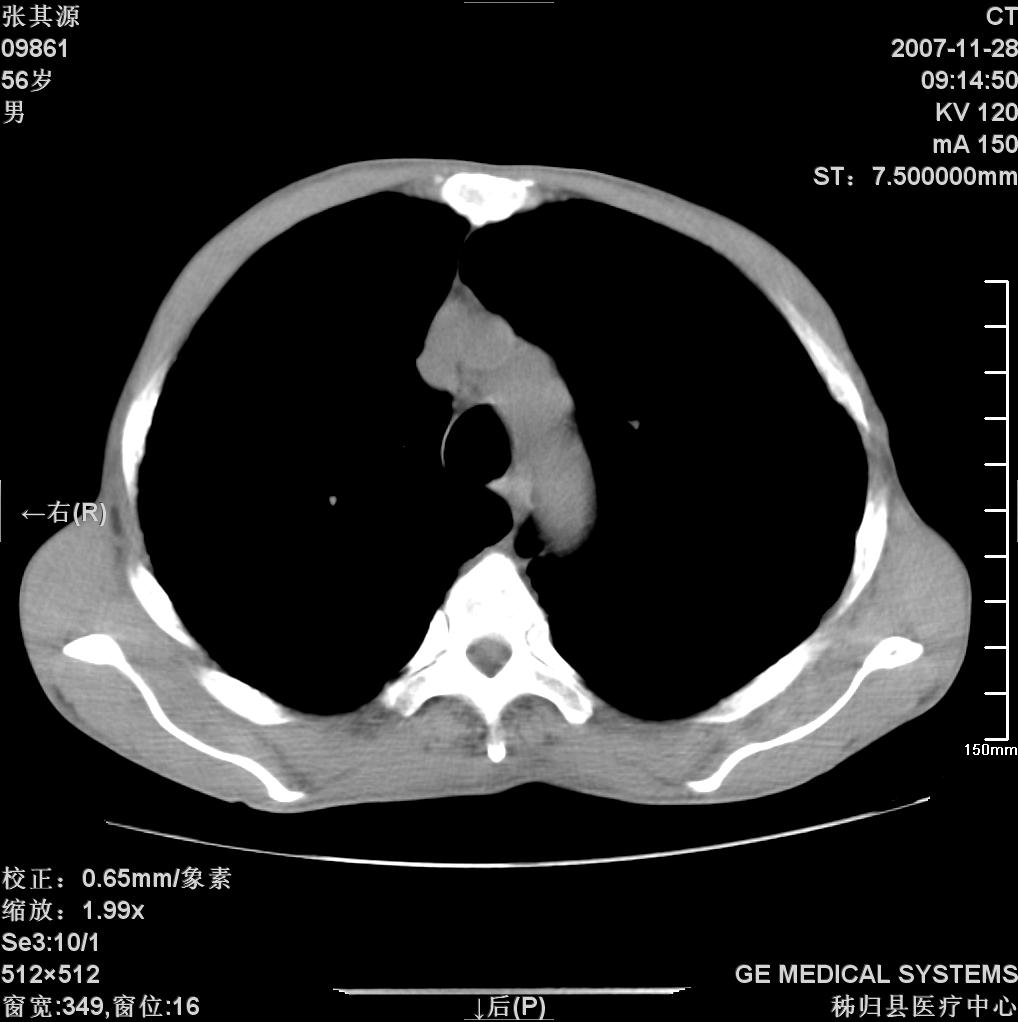

患者因阻塞性黄疸入院,发病前10天持续中等程度发烧.术前检查发现两肺弥漫性病变,请各位大虾会诊,除了考虑急性血源性肺结核外,还有其他什么疾病可能.

考虑tb不排除转移,(隆突处有肿大淋巴结,不好说是结核还是转移引起的)

双肺多发粟粒样病灶,右肺胸膜下结节样病灶,气管前腔静脉后及隆突下均见肿大淋巴结,结合胆道肿瘤病史首先考虑转移。另外心影密度略低,时间格显示,是否有贫血?查明白再手术吧!